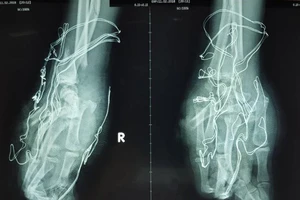

Học sinh 15 tuổi mất trọn bàn tay phải do pháo nổ